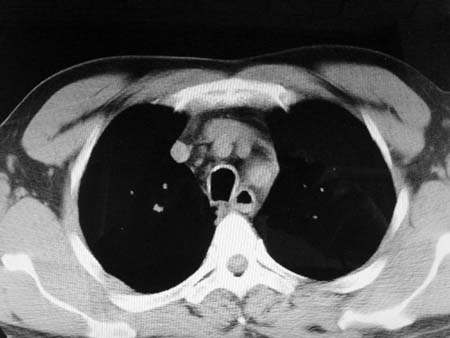

以下是引用qian在2008-4-27 17:02:00的发言:[br]考虑右下肺肺段隔离症伴有感染,建议做增强看看。

以下是引用zsl6918在2008-4-27 17:13:00的发言:[br]考虑右肺下叶炎性病变可能性大,建议抗炎治疗后复查,现有资料不能完全除外肺癌可能。